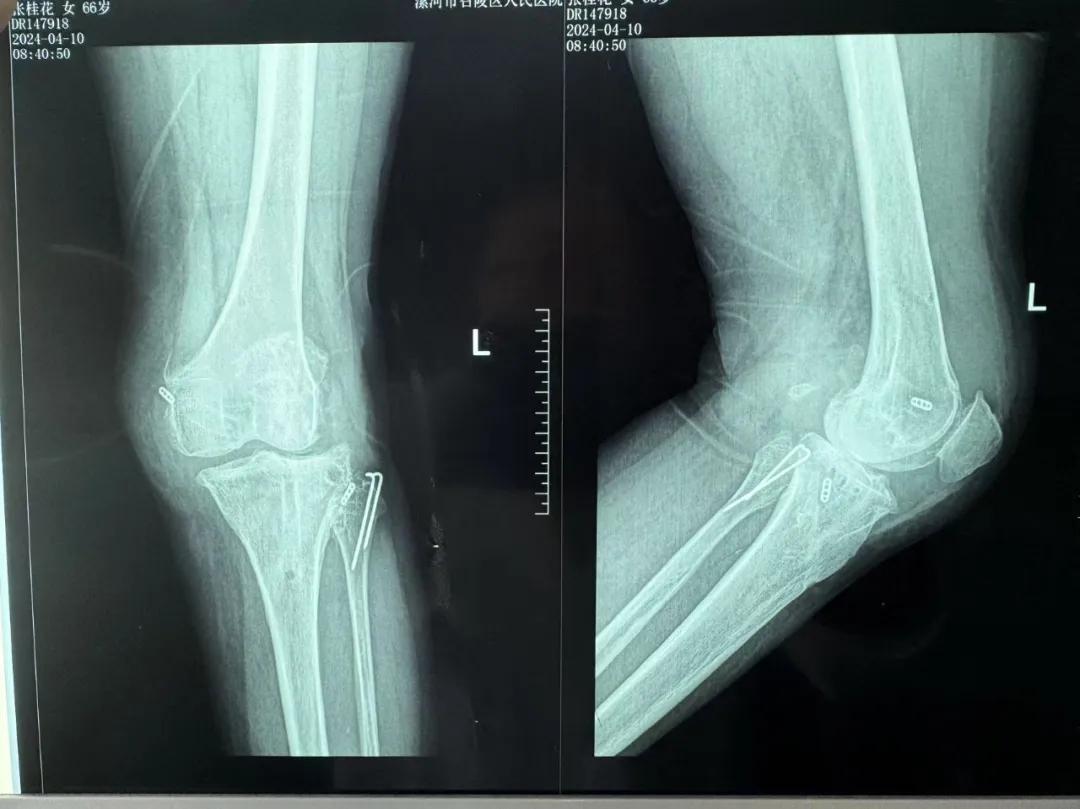

患者來院后,漯河市骨科醫(yī)院(漯河醫(yī)專二附院、漯河市立醫(yī)院)主治醫(yī)師康樂便成了她的管床醫(yī)生。在經(jīng)過詳細(xì)的術(shù)前診斷與檢查后,關(guān)節(jié)外科主任李付彬組織科室團(tuán)隊(duì)針對患者的診斷情況進(jìn)行術(shù)前討論——患者為重度膝關(guān)節(jié)骨關(guān)節(jié)炎,需進(jìn)行人工關(guān)節(jié)置換。但術(shù)前的評估結(jié)果顯示:患者膝關(guān)節(jié)側(cè)方不穩(wěn)定,單純行初次表面膝關(guān)節(jié)置換,術(shù)后仍會存在側(cè)方不穩(wěn)的情況,會影響術(shù)后效果以及假體使用年限,不僅無法完全恢復(fù)膝關(guān)節(jié)功能,還會加重患者的經(jīng)濟(jì)負(fù)擔(dān)。

為了盡可能給患者帶來更好的治療效果,減輕其經(jīng)濟(jì)負(fù)擔(dān),經(jīng)綜合評估后,李付彬主任帶領(lǐng)團(tuán)隊(duì)制定了最終的手術(shù)方案——決定使用髁限制性膝關(guān)節(jié)假體(LCCK)置換膝關(guān)節(jié)。作為解決患者病痛的最優(yōu)方案,這項(xiàng)手術(shù)具體實(shí)施的難度并不小,需要在術(shù)中根據(jù)截骨情況進(jìn)行多次評估和實(shí)時(shí)調(diào)整,這就要求主刀醫(yī)生不僅要具備過硬的專業(yè)技術(shù)與能力,還要能夠結(jié)合自身的經(jīng)驗(yàn)準(zhǔn)確判斷、精準(zhǔn)操作。

手術(shù)過程中,關(guān)節(jié)外科團(tuán)隊(duì)為患者進(jìn)行了標(biāo)準(zhǔn)截骨,經(jīng)過評估,患者膝關(guān)節(jié)仍存在膝關(guān)節(jié)側(cè)方不穩(wěn)定,便按照原定手術(shù)計(jì)劃使用LCCK假體進(jìn)行了膝關(guān)節(jié)置換。經(jīng)過再次評估,患者膝關(guān)節(jié)穩(wěn)定性恢復(fù),下肢力線正常,這臺高難度的LCCK膝關(guān)節(jié)置換手術(shù)在一小時(shí)內(nèi)便順利完成!術(shù)后第二天,患者就能夠自主下床負(fù)重活動,功能恢復(fù)良好。